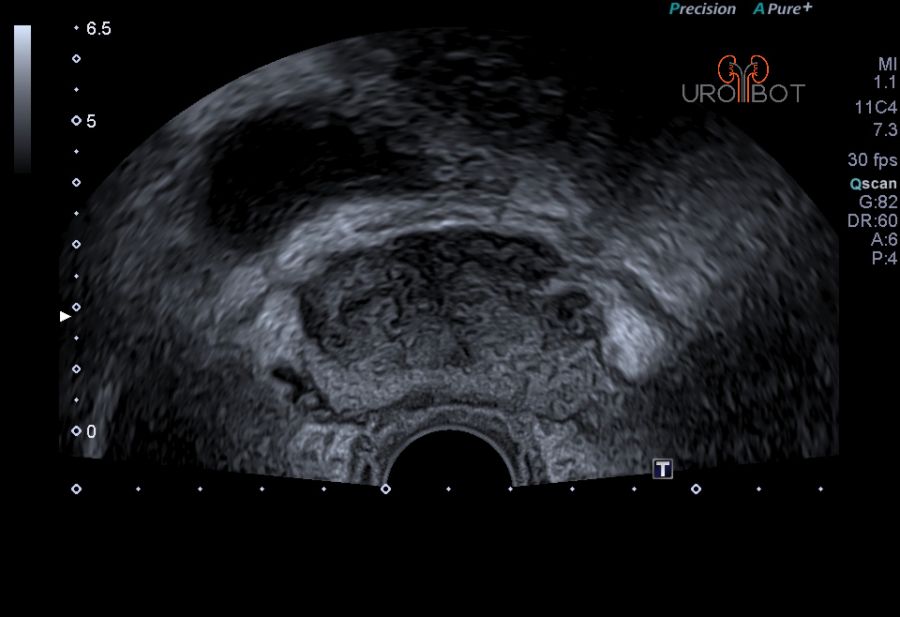

In der Klinik für Urologie am Knappschaftskrankenhaus Bottrop steht seit 10/2017 ein neues Gerät zur Verfügung, welches die Bilder eines 3-Tesla-MRT-Gerätes mit denen eines High-End-Ultraschallgerätes fusionieren kann. Eine Spezialsoftware ermöglicht eine dreidimensionale Rekonstruktion der Prostata, in der die zuvor markierten auffälligen Areale in ihrer räumlichen Lokalisation sichtbar gemacht werden können. Durch die bessere Detektionsrate bei der MRT-Untersuchung lassen sich somit auffällige Areale auf die konventionellen Echtzeit-Ultraschallaufnahmen spiegeln, sodass dadurch eine millimetergenaue Gewebeprobe auffälliger Areale in der Prostata erfolgen kann. Dadurch kann die Entdeckung von bösartigen Prostatatumoren entscheidend verbessert werden.

Das Video zeigt eine sonographische Untersuchung der Prostata, durchgeführt über eine sogenannte transrektale Ultraschallsonde.